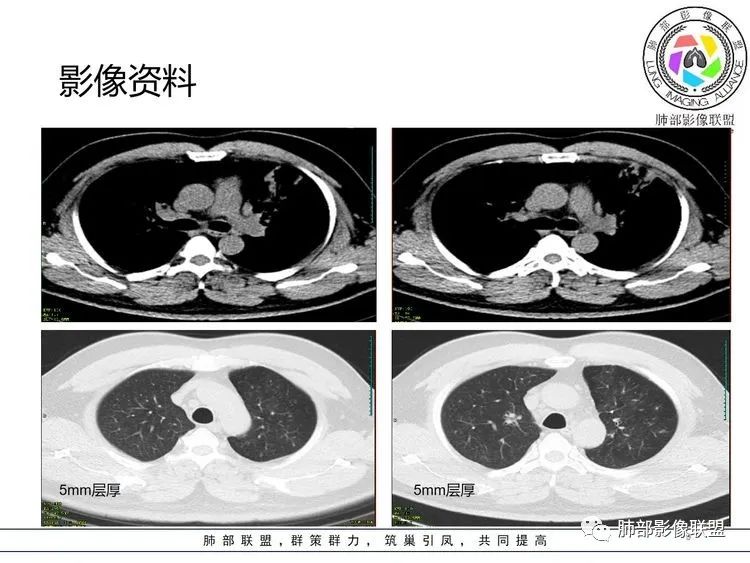

张延军: 克雷白。空洞,叶间裂下坠

青藤之凉: 肺炎克雷伯菌,大家都对了。

肺炎克雷伯菌有局限性,因为痰液粘稠,会造成叶间裂膨出。肺内可能会有蜂窝样改变。有糖尿病、吸烟、支气管病病史者,容易感染肺炎克雷伯菌。可能会有空洞形成,右肺上叶发病最常见。